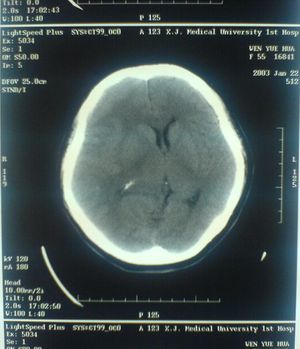

Displaced Ventricles in Brain CT

ويستعمل الأطباء فحوص التصوير المقطعي الحاسوبي لتشخيص كثير من الحالات مثل الأورام والإصابات وتجلطات الدم وكسور العظام. ويساعد التصوير المقطعي الحاسوبي أيضًا في معالجة بعض الأمراض، التي قد تتطلب جراحة بطريقة أخرى. فمثلا،ً يمكن للأطباء استعمال التصوير المقطعي الحاسوبي لإرشادهم إلى إدخال القثطار (أنبوب رفيع) إلى خُرّآج في الجسم لسحب الصديد من المنطقة الملوثّة.